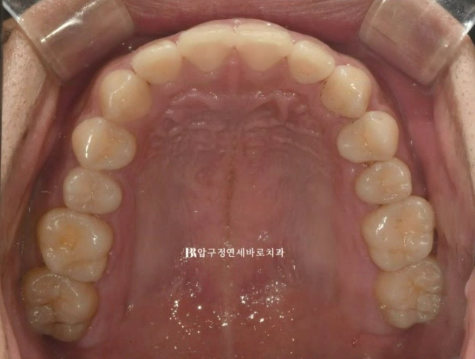

윗니는 가지런했지만

24.02